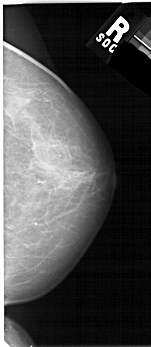

A_1686_1.RIGHT_MLO

RIGHT_MLO LINES 5326 PIXELS_PER_LINE 2686 BITS_PER_PIXEL 12 RESOLUTION 43.5 NON_OVERLAY

FILE: A_1686_1.LEFT_CC.OVERLAY

TOTAL_ABNORMALITIES 1

ABNORMALITY 1

LESION_TYPE MASS SHAPE IRREGULAR MARGINS ILL_DEFINED

ASSESSMENT 4

SUBTLETY 3

PATHOLOGY BENIGN

TOTAL_OUTLINES 1

BOUNDARY